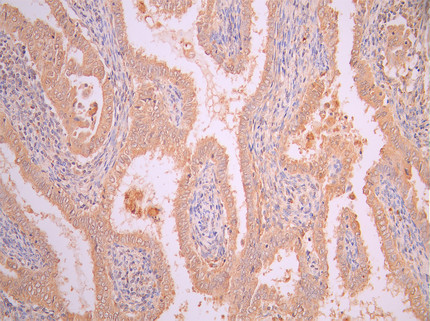

• IHC image of CSB-RA008424MA2HU diluted at 1:50 and staining in paraffin-embedded human endometrial cancer performed on a Leica BondTM system. After dewaxing and hydration, antigen retrieval was mediated by high pressure in a citrate buffer (pH 6.0). Section was blocked with 10% normal goat serum 30min at RT. Then primary antibody (1% BSA) was incubated at 4°C overnight. The primary is detected by a Anti-Human lgG, Fcy Fragment Specific labeled by HRP and visualized using 0.05% DAB.